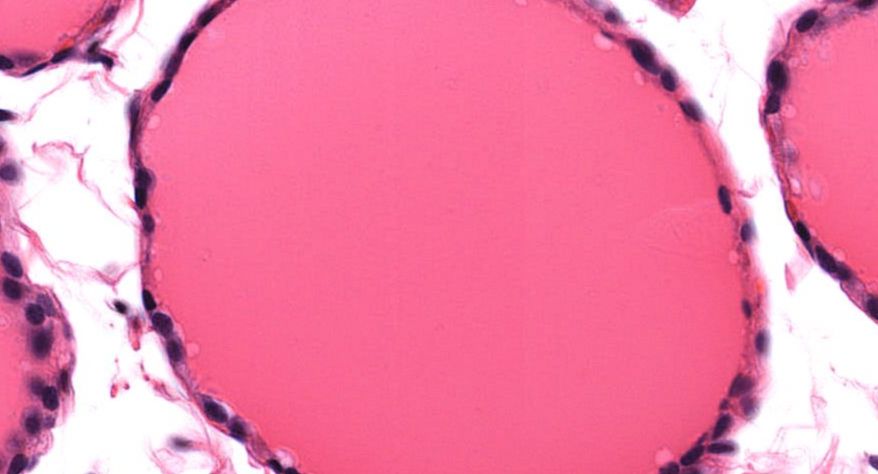

低倍镜观察:1. 被膜:由薄层结缔组织组成。2. 实质:由许多大小不等的滤泡构成。滤泡壁是单层立方上皮细胞,滤泡腔内充满粉红色匀质胶状物,滤泡之间的结缔组织内有丰富的血管。高倍镜观察:1. 滤泡:滤泡壁的单层滤泡上皮细胞一般呈低柱状或立方状,胞质着浅色,细胞核呈圆形。滤泡腔内充满了粉红色匀质胶质。2. 滤泡旁细胞:体积较大,呈圆形或椭圆形;细胞核较大,呈圆形,着色较浅,细胞质染色也较浅。细胞或嵌在滤泡壁上或成团分布于滤泡之间。3. 间质:由结缔组织组成。位于滤泡之间。其中含有丰富的毛细血管及三五成群的滤泡旁细胞。

4.胶质